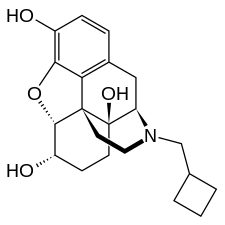

Opioid antagonists and inverse agonists

- 4-Caffeoyl-1,5-quinide

- 5'-Guanidinonaltrindole

- β-Funaltrexamine

- 6β-Naltrexol

- 6β-Naltrexol-d4

- Alvimopan

- AT-076

- Binaltorphimine

- BU09059

- Buprenorphine

- Chlornaltrexamine

- Clocinnamox

- Cyclazocine

- Cyprodime

- Diacetylnalorphine

- Diprenorphine (M5050)

- Fedotozine

- ICI-174864

- J-113,397

- JDTic

- JTC-801

- Levallorphan

- LY-2456302

- LY-255582

- Methocinnamox

- Methylnaltrexone

- ML350

- Naldemedine

- Nalfurafine

- Nalmefene

- Nalmexone

- Nalodeine (N-allylnorcodeine)

- Naloxazone

- Naloxegol

- Naloxol

- Naloxonazine

- Naloxone

- Naloxone benzoylhydrazone

- Nalorphine

- Naltrexone

- Naltriben

- Naltrindole

- Norbinaltorphimine

- Oxilorphan

- PF-4455242

- S-allyl-3-hydroxy-17-thioniamorphinan (SAHTM)

- Samidorphan

- SR-16430